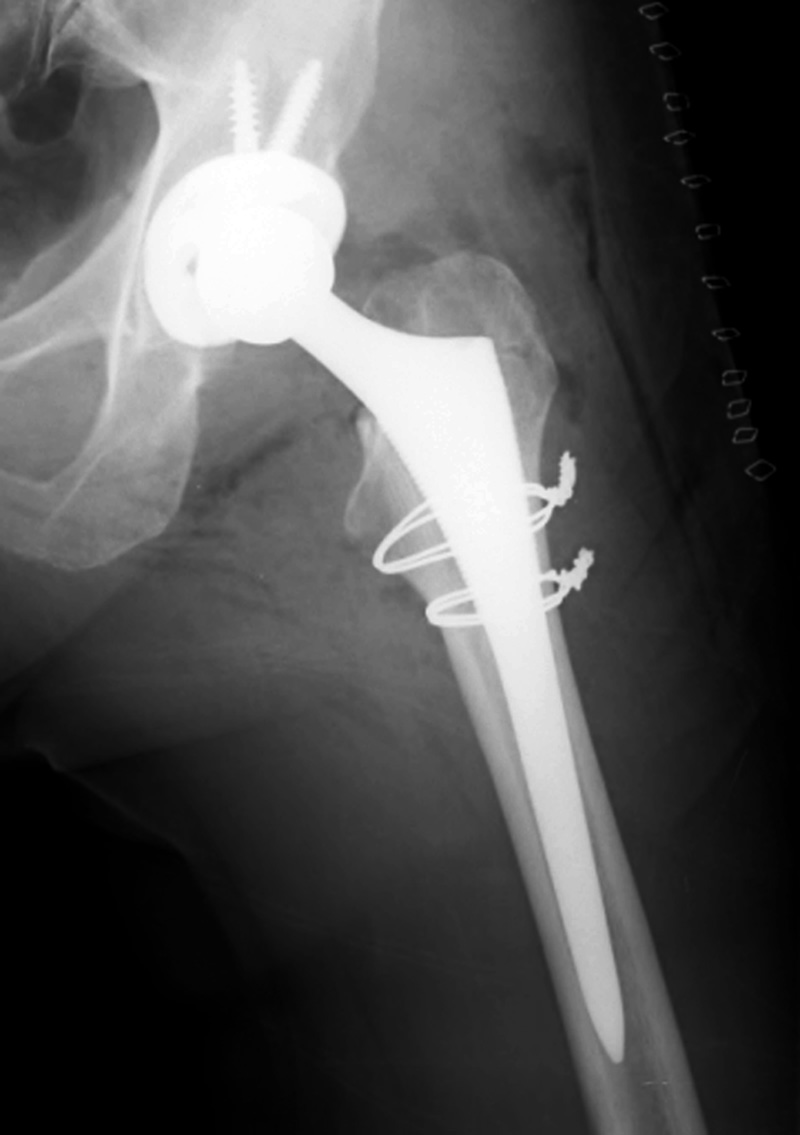

Revision total hip prosthesis |

The revision prosthesis was placed because of an earlier periprosthetic fracture. There are two cable wires proximally and two cerclage wires distally. |